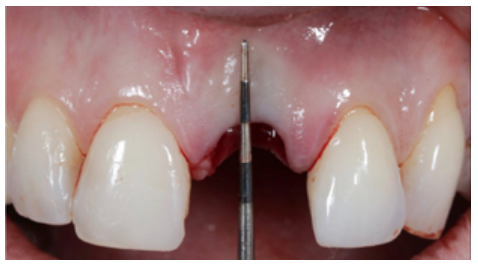

Using a Lucas-type curette spoon and a CP12 periodontal probe, the state of the alveolus was checked and found to be completely intact, except for the vestibular region, where there was a defect in the coronal-apical direction of 4 mm (Figure 4).